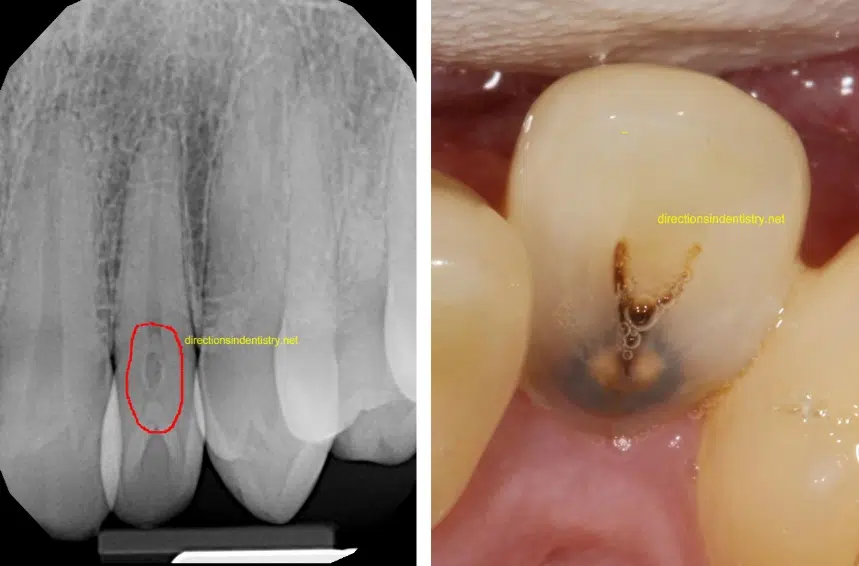

Dens in dente

نقصی تکاملی در تشکیل دندان که در نتیجه ی چین خوردن اپیتلیوم تشکیل دهنده ی تاج دندان به داخل فضای پالپی ایجاد می شود. پس از معدنی شدن ، در نتیجه ی این چین خوردگی ، داخل فضای پالپی عاج و مینا خواهیم داشت که نمای رادیوگرافیک آن مانند حضور یک دندان کوچک داخل دندان است‌.